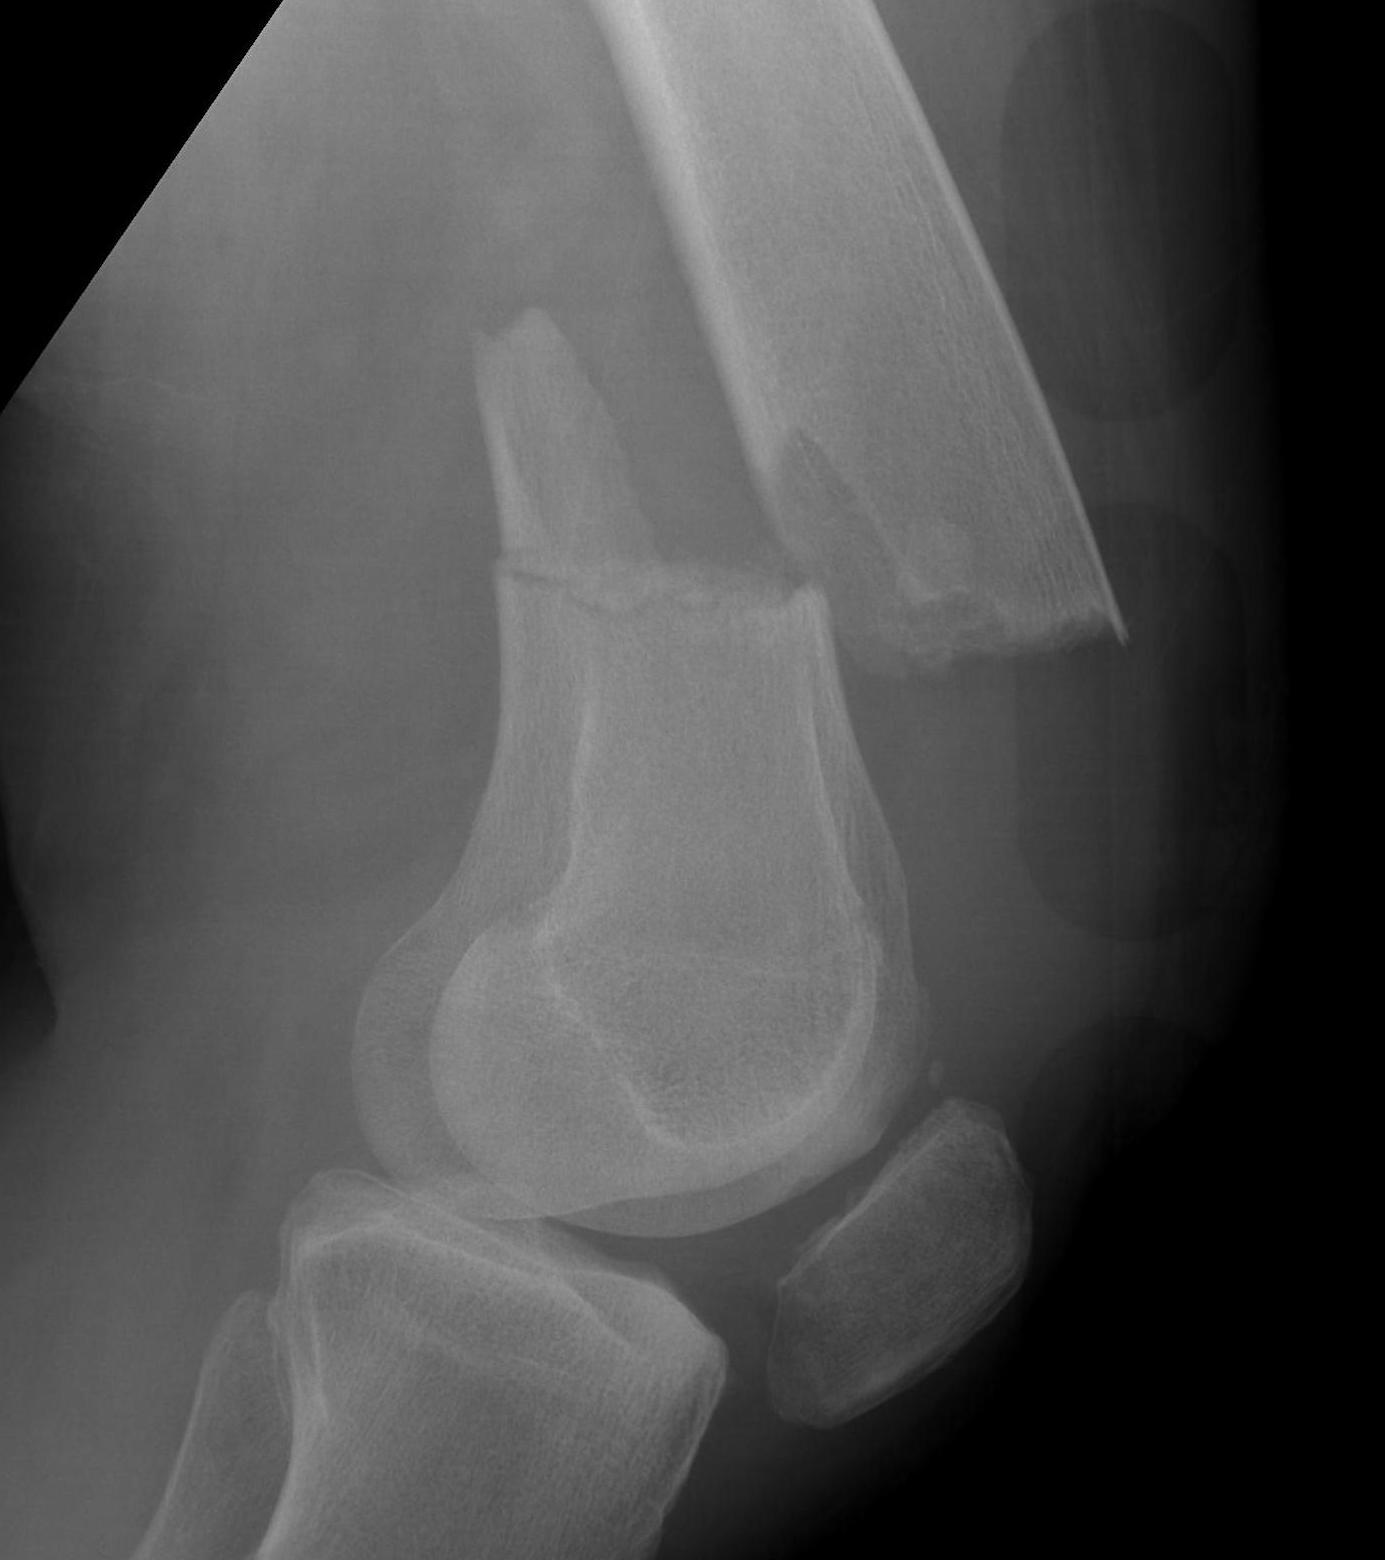

AO Type A: Supracondylar / Extra-condylar

Xray

Options

Lateral plate

Retrograde IM nail